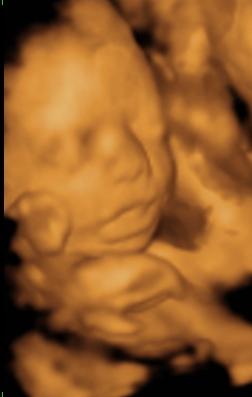

Remélem kihúzzuk még pár hétig…

Meg sem mertem kérdezni, most milyen esélyei lennének…

Barbus mennyivel született?

Csak a külső van nyitva egy ujjnyira és megrövidült a méhnyak.

Tüdőérlelőről nem volt szó, csak kérdeztem, hogy ha májusban indulna meg, akkor a Jánosba induljunk-e rögtön, de mondta, hogy nem, mert lehet még infúzióval bent tudják tartani, gondolom akkor kapna tüdőérlelőt is.

Igazából ha már 2 kiló felett lenne Zsombor, nyugodtabb lennék, de másfél még nagyon kevés…